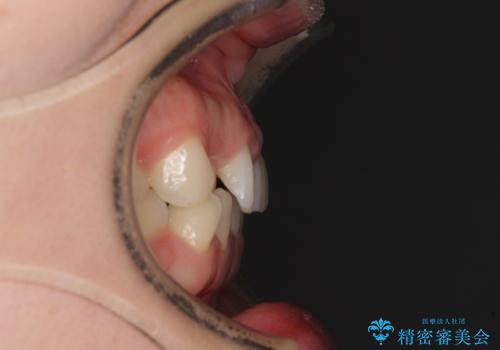

- 前歯の隙間やクロスバイトを気にして来院された患者様です。

結婚式の予定があり、可能であれば結婚式までに治療を終えたいとのことで、短期間で治療をおける可能性の高いワイヤー装置にて矯正治療を行うこととしました。